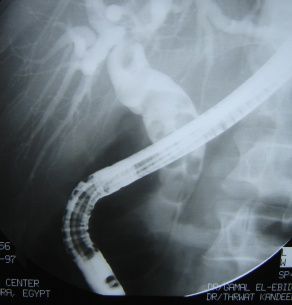

内視鏡的逆行性胆管膵管造影 (ERCP Endoscopic retrograde cholangiopancreatography)

総胆管に内視鏡を挿入してその先に付いた細いチューブ胃から造影剤を注入し胆道系膵管を直接造影する安全性の高い検査です.